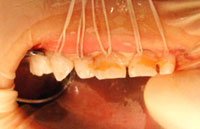

これは6歳のこどもの歯列です

犬歯やその後ろの歯はまだ根の部分が殆ど出来ていません

右の写真は6歳児の歯の様子を、歯茎を透明にして見せたものです。

永久歯は歯の根が3分の2ほどできたところで生えてきます。

つまり、その前に乳歯が虫歯になって抜いてしまっても、歯のないまま過ごさなくてはならないのです。